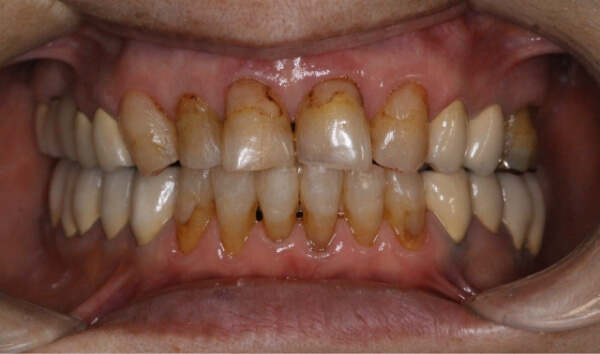

保定

日々歯がキレイに並んでいく様子を見て患者様も喜びを感じ、治療を終えることができました。

患者様も、たった6ケ月で「すきっ歯」が解消されたことにとても感動されており、心置き無く笑顔に慣れると喜んでいました。